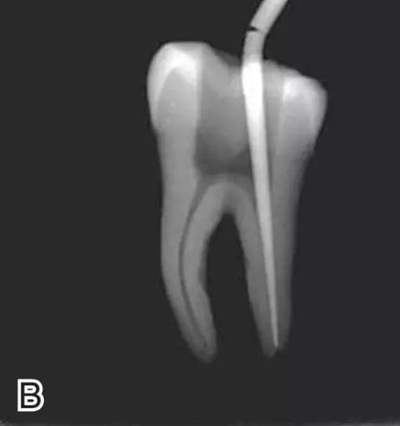

選擇的小號垂直加壓器應(yīng)能自由到達(dá)距根尖4~5 mm(有學(xué)者提出3~4 mm)的位置并能輕微接觸根管壁;中號垂直加壓器應(yīng)能自由到達(dá)距根尖7~8 mm的位置并能輕微接觸根管壁;大號垂直加壓器應(yīng)能自由到達(dá)距根尖10~11 mm的位置并能輕微接觸根管壁。用橡皮片做好標(biāo)記(圖2)。

圖2 選擇垂直加壓器,A.試垂直加壓器 B.垂直加壓器在根內(nèi)的位置